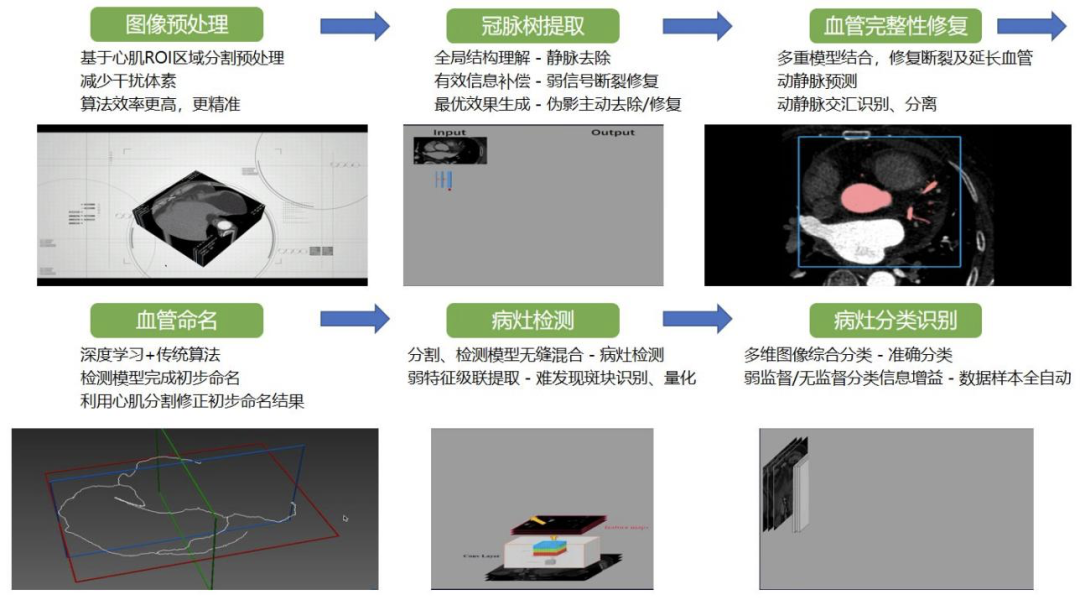

整个流程的详细步骤是:第一步做预处理,然后提取冠脉树,其中会有很多断裂和各种各样的瑕疵,需要基于解剖学知识的算法来做血管的修复和连接;另外,还需要给血管进行命名,重建出冠脉树,并在不同的血管上做病灶检测以及分类和识别,每一个环节都包含很多细节。

可见,2.0 产品相对于 1.0 产品有很大的区别,它由多个流程串联而成,每一步之间都有一些关系和影响。